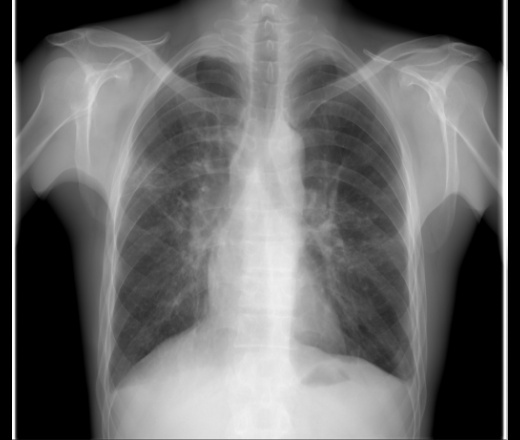

й в легких

Лей в легких 106 фотографий